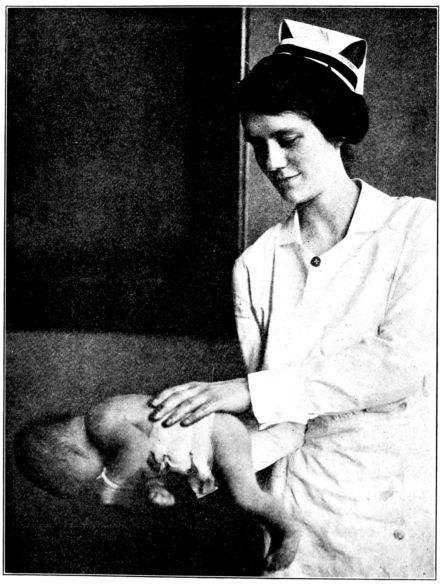

| 167. | Proper method of carrying baby | 487 |